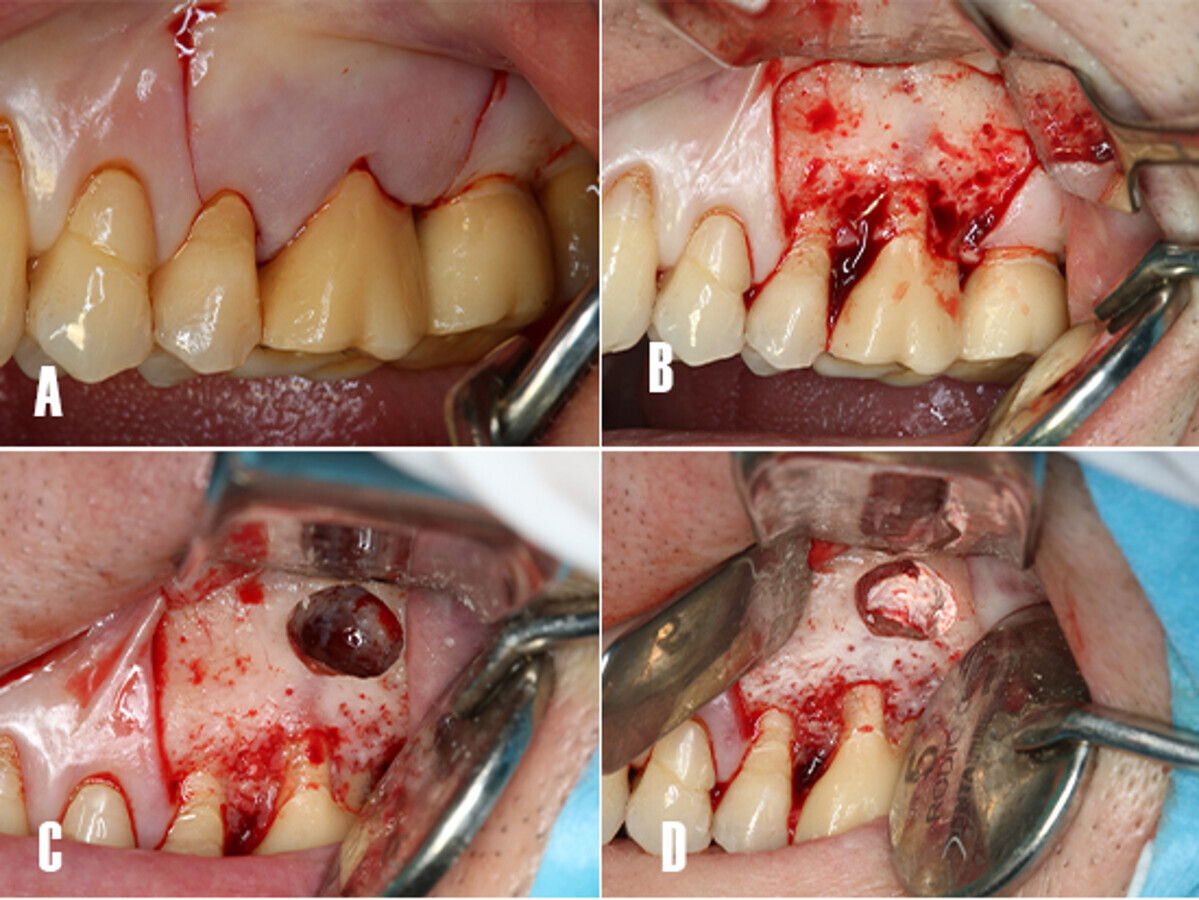

La cirugía se realizó bajo anestesia local infiltrativa con articaína al 4% (1:100,000) (Inibsa; Lliça de Vall, Barcelona, Spain). Se realizó una incisión a espesor completo con una hoja bisturí 15c, para elevar un colgajo mucoperióstico de Newmann trapezoidal. Tras la elevación del colgajo se realizó una osteotomía con una fresa redonda de carburo tungsteno 0.27mm de diámetro (Jota AG, Rüthi SG, Switzerland) empleando una pieza de mano recta 1:1 (Synea Vision, W&H Dentalwerk, Bürmoos, Austria). Tras acceder a la cripta ósea, se realizó la resección de la porción apical de las raíces, se instrumentó una cavidad retrógrada de 3 mm de profundidad con puntas ultrasónicas (Piezomed, W&H Dentalwerk, Bürmoos, Austria). La hemostasia se realizó empleando gasas estériles impregnadas con epinefrina (B. Braun, 1 mg/ml; Rubí, Barcelona, Spain) y con tiras de politetrafluoretileno (PTFE) previamente esterilizadas en autoclave, y que se compactaron dentro de la cripta ósea (Fig. 4).

Figura 4. Técnica quirúrgica. A) Incisión a espesor total para elevar un colgajo de Newmann trapezoidal. B) Despegamiento del colgajo. Se observa la cortical vestibular intacta. C) Ostectomía de acceso a la cripta ósea, nótese el tamaño de la lesión. D) Hemostasia: esta se obtiene aplicando gasas impregnadas con epinefrina y tiras de PTFE compactadas hacia las paredes de la cripta ósea, y surte un efecto de barrera mecánica.